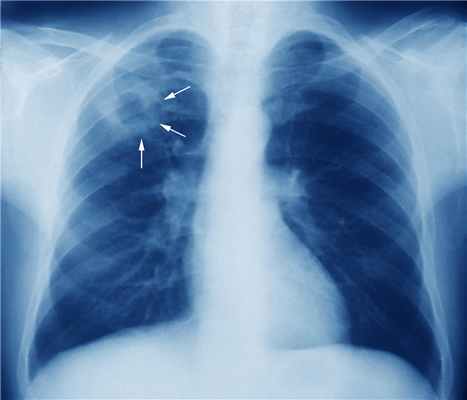

- флюорография;

- рентгенография легких, позвоночника и суставов;

- Первичный туберкулезный комплекс. Возникает при первичном заражении туберкулезом и встречается, как правило, среди детей. Протекает без выраженных симптомов, рентгенологически напоминает пневмонию, поэтому диагностика затруднена, не заразен. Небольшой очаг в большинстве случаев закрывается капсулой, и болезнь дальше не развивается.

- Туберкулез внутригрудных лимфатических узлов. Характеризуется распространением туберкулезных очагов в обоих легких и поражением лимфоузлов.

- Диссеминированный туберкулез легких. По всей поверхности легких образуются крошечные воспалительные бугорки. Может быть острым или хроническим, протекает тяжело (с лихорадкой, интоксикацией) и волнообразно.

- Очаговый туберкулез легких. В легком образуется от одного до нескольких воспалительных очагов не более 1 см в диаметре. Может протекать бессимптомно или с невысокой температурой, недомоганием.

- Инфильтративный туберкулез легких. Является одним из осложнений очагового туберкулеза. Протекает тяжело, с длительной лихорадкой, потерей веса, кашлем, может наблюдаться кровохарканье.

- Казеозная пневмония. Тяжелая форма легочного туберкулеза, развивается остро, с тяжелой интоксикацией, лихорадкой. Характеризуется массивным воспалением и затем распадом легочной ткани с образованием полостей в легком. Чаще всего возникает у больных с ослабленным иммунитетом.

- Туберкулема легких. В ткани легкого образуется инкапсулированный очаг более 1 см в диаметре, внутри которого происходит распад легочной ткани.

- Кавернозный туберкулез легких. Тяжелая форма туберкулеза, при которой происходит деструкция легочной ткани и образуются большие каверны (полости) в легком. Возникает как осложнение других форм туберкулеза.

- Фиброзно-кавернозный туберкулез легких. Является завершающим этапом кавернозного туберкулеза, когда окончательно формируется полость в легком.

- Цирротический туберкулез легких. Последняя стадия туберкулеза легких, характеризуется замещением легочной ткани на рубцовую. Встречается в 0,1-8% случаев, в основном у нелеченых или неправильно леченых пациентов. Для формирования данной формы требуются годы болезни.

- Туберкулезный плеврит. Воспалительный процесс поражает оболочку легких – плевру. Может развиться как осложнение туберкулеза легких или как самостоятельное заболевание, особенно у молодых людей.

Рентгенологическое исследование структуры легких с целью диагностики различных патологий.

Исследование, позволяющее получить данные о состоянии органов грудной клетки и средостения.